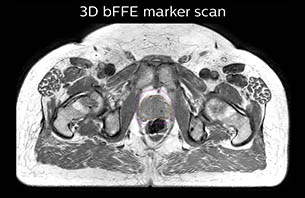

Using the mDIXON and 3D bFFE images, the RT planner marks the position of the nickel-titanium fiducial markers, and contours are transferred to the digitally reconstructed radiographs (DRRs). Reference image matching is based on these markers. “In the rare cases, where visualization of the fiducial markers fails, we do a CT to confirm their location,” Dr. Keyriläinen notes.

A 77-year-old male with prostate cancer cT3aN0M0, Gleason 8 and PSA 52 μg/L referred to androgen deprivation and radiation therapy with a prescribed dose of 50 Gy to the pelvic lymph node regions and 76 Gy to the prostate.

The 3D T1W FFE mDIXON sequence provides in-phase, water and fat images in one acquisition. Target and organs-at-risk are delineated on the 3D T2W TSE images. Prostate GTV is shown in orange, PTV in purple. The 3D bFFE sequence is used by the planner to mark the position of the fiducial markers (gold anchors) and contours are transferred to the digitally reconstructed radiographs (DRRs).